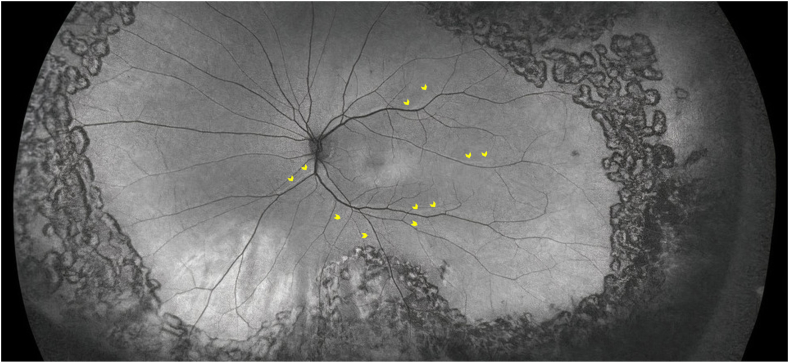

One month following PFO removal, Snellen best-corrected visual acuity was 20/30. The patient complained of significant distortion, and vertical and horizontal metamorphopsia scores were 0.6 and 0.5, respectively, as assessed using the M-chart (M-CHARTS™, Inami & Co,Ltd, 135 Japan). Aniseikonia test (Awaya New Aniseikonia Tests, Handaya Co Ltd, 136 Tokyo, Japan) demonstrated an aniseikonia score of 2. Optos Wide-field FAF (Optos Inc., Malborough, MA, USA) was repeated and confirmed the presence of unchanged RVPs at 1 month (Fig. 1).

Fig. 1.

Wide-field autofluorescence imaging at postoperative month 1 with yellow arrowheads indicating the direction of retinal displacement/stretch inferior and temporally in the same direction as the induced flow of subretinal fluid by the perfluorocarbon liquid. (For interpretation of the references to colour in this figure legend, the reader is referred to the Web version of this article.)